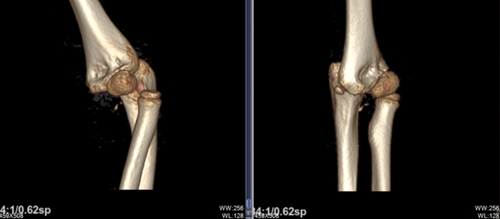

02 病例二

另有一名 8 歲男孩,在家中玩耍時(shí)不慎從椅子上摔落,左胳膊當(dāng)場(chǎng)彎成畸形,被家長(zhǎng)緊急帶至青島市婦女兒童醫(yī)院兒童骨折整復(fù)門診。經(jīng)拍片檢查確認(rèn)是左肘關(guān)節(jié)脫位合并左尺骨近端、左肱骨遠(yuǎn)端多處骨折。隨后,該門診醫(yī)生為患兒進(jìn)行了手法整復(fù),孩子受傷的胳膊恢復(fù)原貌,拍片顯示骨折處已經(jīng)復(fù)位成功,家長(zhǎng)連連道謝。

復(fù)位前

復(fù)位后